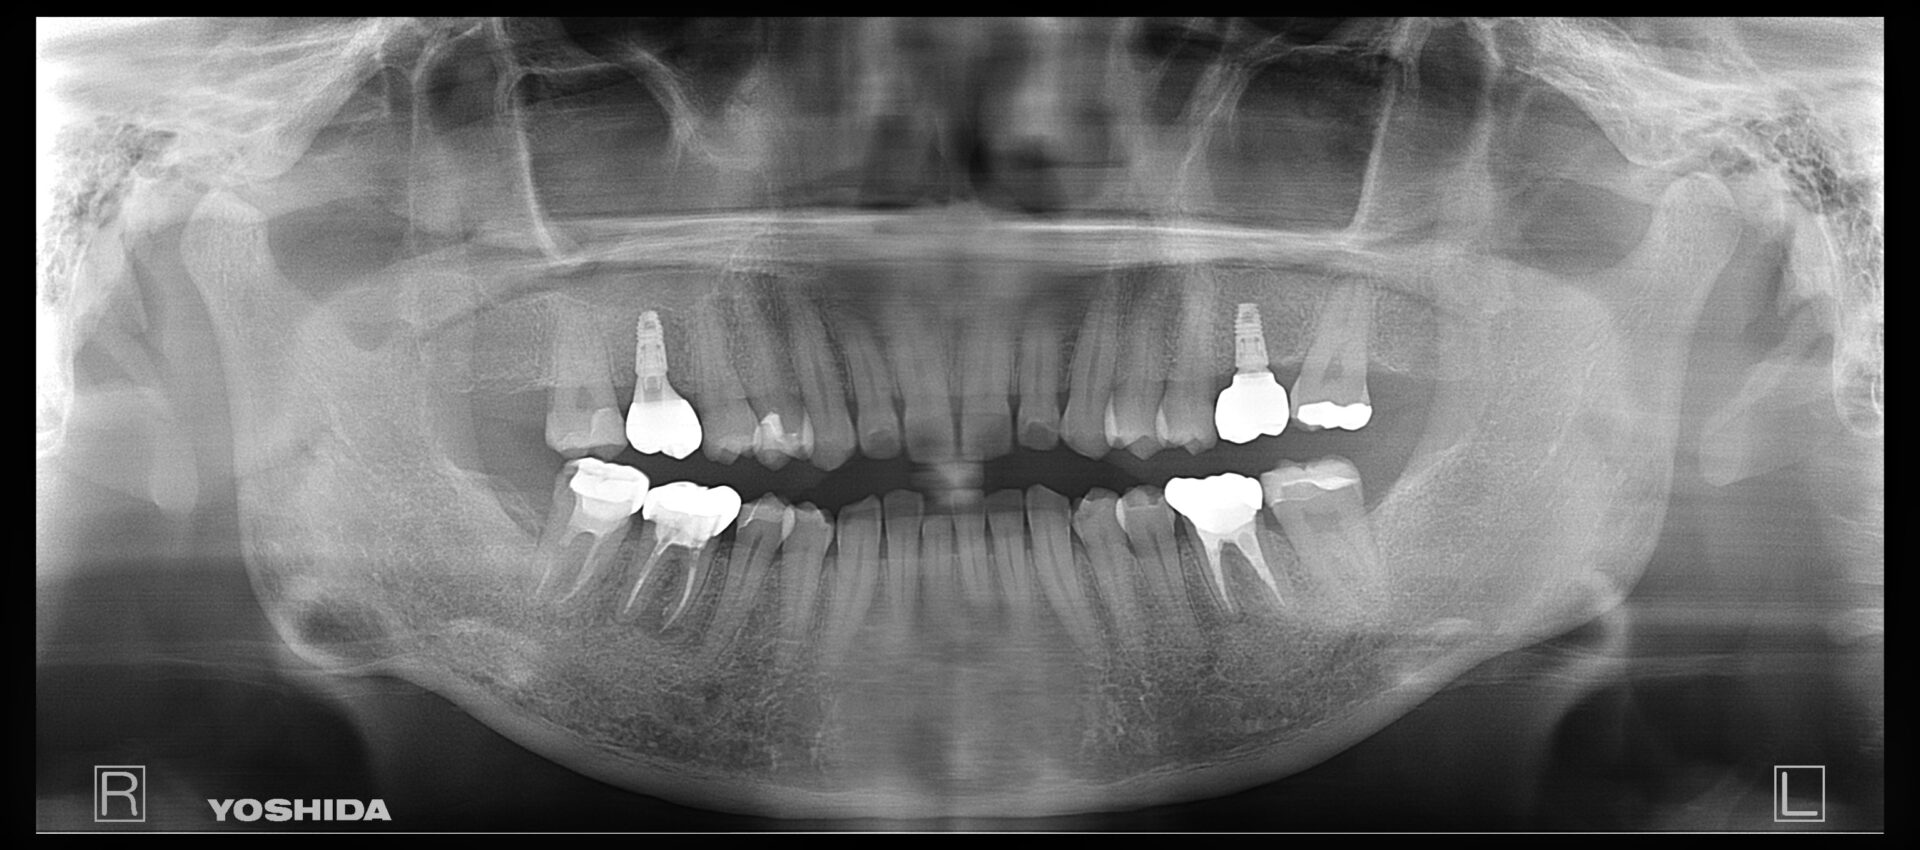

60代男性

R5.8

右下4番破折の疑い

R5.12

右下4番抜歯後経過観察

画像

R6.12

インプラント埋入後、上部の被せ物を被せました

費用 約43万円

治療期間 1年4ヶ月

右下4番にフィステルが頻繁にできており、他院では抜歯のみと説明を受け、他の治療を検討できないかと当院にお越しになられました。

根管治療を数回行い、フィステルの出現は小さくなり頻度も減ったが抜歯が最善との判断に至りました。

抜歯をし、インプラントをご希望されていたのでしっかり5ケ月かけて経過を観察し、インプラントオペを行いました。